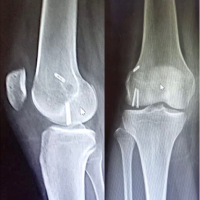

The patient was scheduled for revision arthroplasty. The surgery was undertaken 2 weeks after, and loosening of acetabular cup was confirmed intraoperatively. There were no signs of loosening of the femoral component or infection. Samples were sent to detect possible infection. Loosen cup was removed and exchanged to a larger tantalum cup. The post-operative course was uneventful, and a full recovery was succeeded. At 2, 6, and 12-month follow-up the patient had a painless range of motion and had fully returned to her activities (Fig. 7). At a final follow-up at 18 months, the patient presented with a significant improvement in function and quality of life compared to the pre-operative evaluation. Her pain was limited from a Visual Analog Scale (VAS) = 7 preoperatively to VAS = 2 postoperatively.

Figure 7: Post-operative imaging after revision surgery.